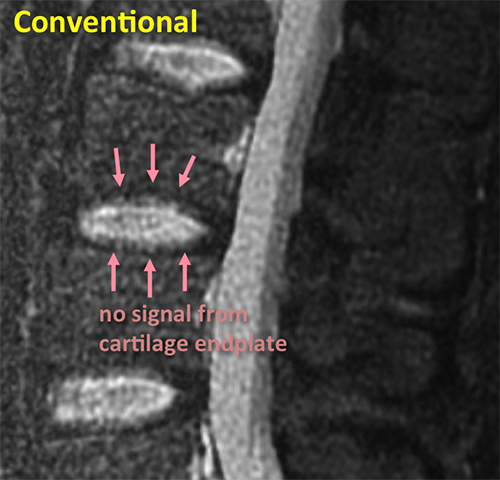

Spine Conventional

This conventional MRI of a spine shows cartilage endplates with low signal intensity, making it difficult to evaluate them.